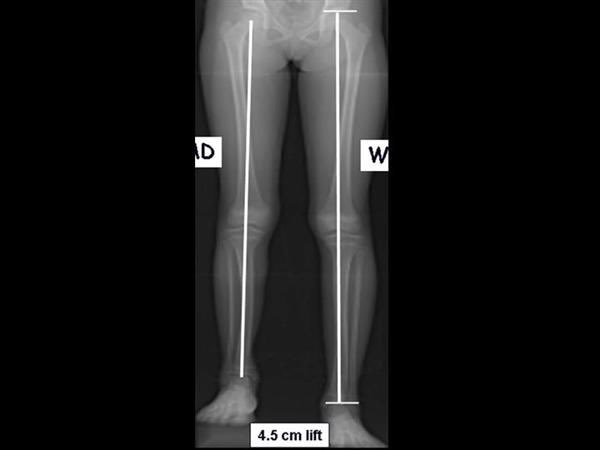

٢)في البدايه الأهل ظنوا ان ممكن شي طبيعي و شوي شوي بيختفي مع الوقت بس الموضوع استمر و تطور و صار ما يقدر ينزل القدم اليسرى نهائيا على الارض و اذا نزلها يصاحبها ميلان في الظهر و يمشي بطريقه غير صحيحه

٤)وقتها كان في شد عضلي شديد في وتر العرقوب من كثر ما كان يمشي الطفل على اطراف اصابعه لتعويض فرق الطول بين الرجلين وكان الشد قريب يتحول إلى قصر و تشوه للمفصل و نضطر للتدخل الجراحي